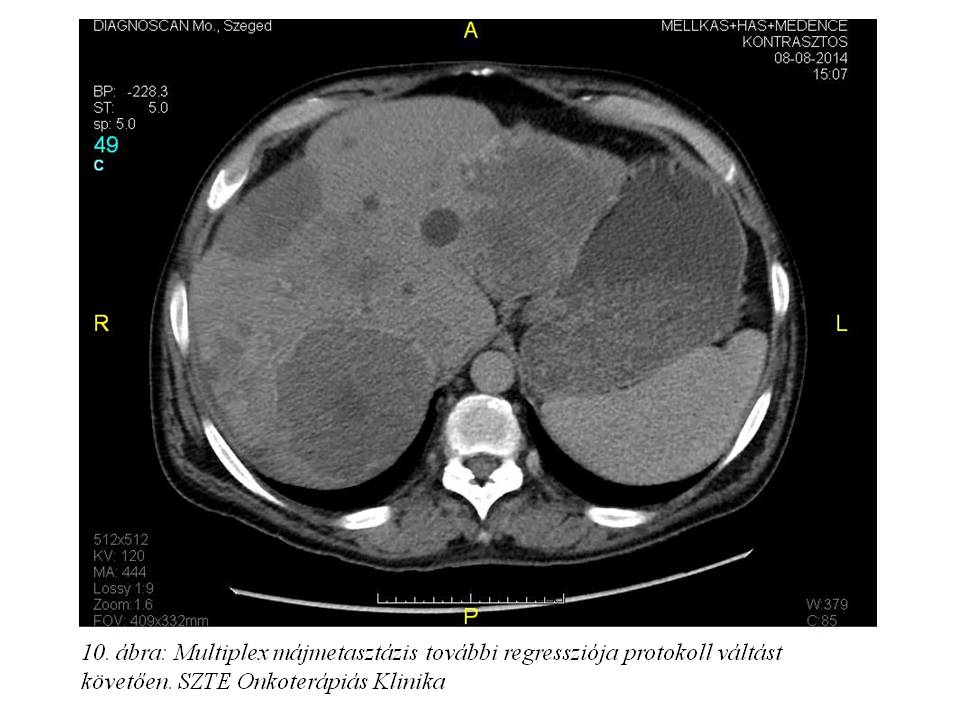

A fentiek értelmében a 16. ciklustól az oxaliplatin adásától eltekintettünk, kezelését DeGramont protokoll (Leucovorin + 5FU bolus + 5FU folyamatos infúzióban) szerint folytattuk. 2014. december 29-ig összesen 11 ciklust kapott. Az ez idő alatt elvégzett re-staging has-kismedence CT további regressziót írt le (2014.08.08. 10. ábra, 2014.10.08. 11. ábra, 2014.12.04. 12. ábra), a mellkas CT-n tüdőmetasztázis továbbra sem detektálható, a tumormarkerek tovább csökkentek (CEA: 0,8 ng/ml, CA 19-9: 7,32 U/ml), májfunkciós enzimek értéke normális.